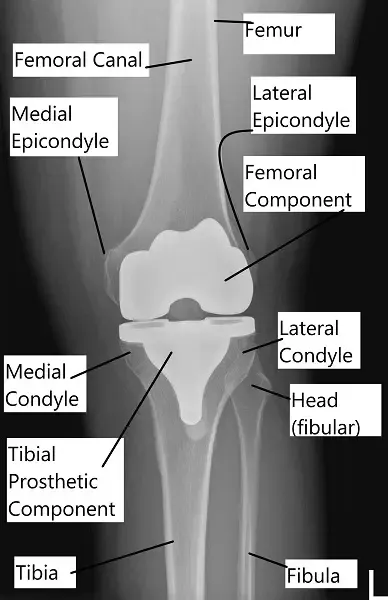

The above images show the prosthetic knee replacement components from the front and the back. The femoral component (posterior stabilized) has a cam mechanism which allows posterior translation of the femur on the tibial post of the bearing surface.

The femoral rollback aids in achieving deeper flexion which in a normal knee is done by the knee ligaments. The polyethylene insert is made of highly cross linked polyethylene, which is resistant to wear and tear. The keel of the tibial component is fixed in the upper part of the shin bone using bone cement.